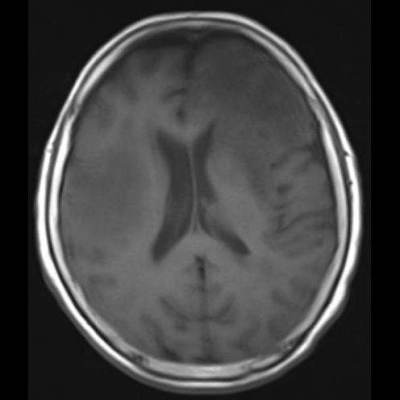

- (A) Her iki periventriküler beyaz cevherde aksiyel T2A, FLAIR serilerde hiperintens, T1A hipointens geniş ödem alanları (oklar) izlenmektedir. Sol frontalde T2A’da hipointens kitle lezyonuna (ok) dikkat ediniz.

- Genellikle supratentoriyal alanda, bazal ganglion, periventriküler beyaz cevher, orta hat ve korpus kallozum vb. yerleşme eğiliminde tek veya multipl kitleler şeklinde görülür.

- Kitleler çoğunlukla solid ve homojendir.

- MRG’de, lenfomalar tipik olarak T2A sekanslarda hipointens olup DAG’de belirgin difüzyon kısıtlanması gösterirler.